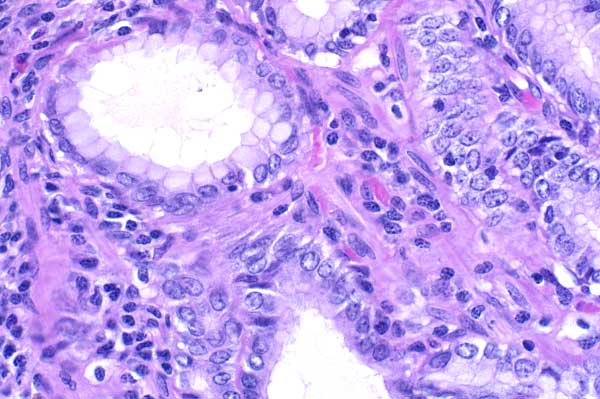

40x   |   Hematoxylin and Eosin

Ectatic gland that contains lighly basophilic bacilli.